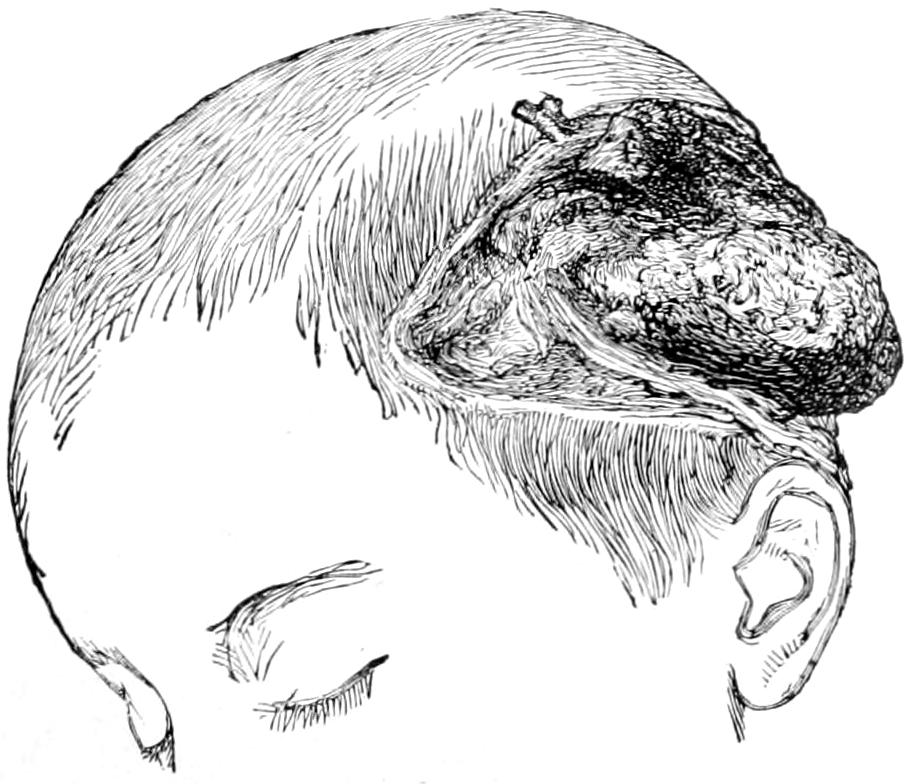

Fig. 1

Congenital hypertrophy: gigantism of both lower extremities. (Case of Dr. Graefe [Sandusky].)